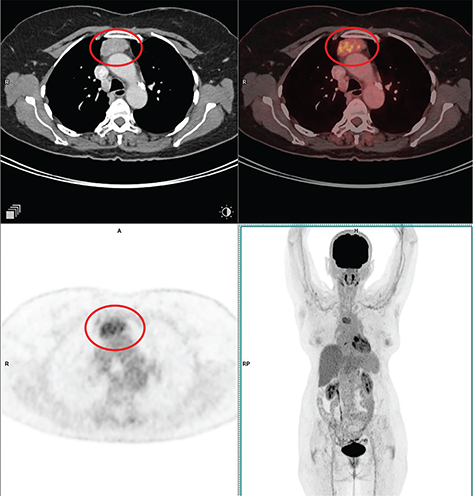

According to histological characteristics, thymomas are divided into five different types: type A thymoma (containing an unusual form), type AB thymoma, type B thymoma (divided into B1, B2, and B3 thymomas), micronodular thymoma with lymphoid stroma, and metaplastic thymoma (22). The presence of FDG uptake in the normal and hyperplastic thymus, especially in younger adults and children, limits the role of 18F-FDG PET/CT in thymoma imaging. Physiological uptake in the thymus has been reported in 28% of patients under 40 years of age and up to 73% in children under 13 years of age (26). Although research has been limited, higher grade tumors tend to have higher FDG activity, 18F-FDG PET/CT has not been shown to reliably distinguish between different grades of thymic tumors (27, 28). An example of typical thymoma is shown in Figure 1.

Fig 1

Figure 1. Type A thymoma. Anterior mediastinal mass that was pathologically confirmed as type A thymoma. FDG PET/CT images include axial CT (top left panel), fused axial PET/CT (top right panel), axial PET (bottom left panel), and maximum intensity projection (MIP) PET image (bottom right panel). In the red circle, there is a soft tissue density mass with well-defined contour showing homogenous enhancement in CT with moderate FDG uptake on PET. No evidence of infiltration of adjacent structures. No other metabolically active disease in the whole-body survey.